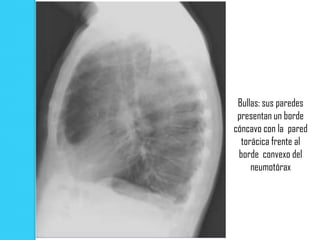

Bullas: sus paredes

presentan un borde

cóncavo con la pared

torácica frente al borde

convexo del neumotórax

Bullas: sus paredes presentan un borde cóncavo con la pared torácica frente al borde convexo del neumotórax